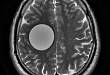

2017.09.14病例挑战:颅内囊性病变

颅内囊性病变在临床中较为常见,引起颅内病变的种类较多,根据起源部位的不同大多可以缩小鉴别诊断的范围。